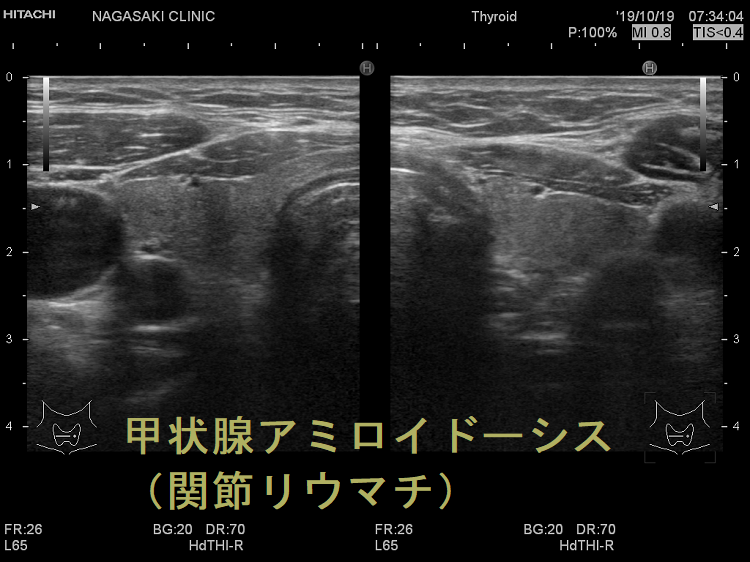

- AAアミロイドーシス:関節リウマチに続発[慢性炎症時, 肝臓から産出される急性期蛋白の血清アミロイドA(SAA)の代謝産物アミロイドA], 家族性地中海熱(周期的に起こる発熱・関節炎・胸膜炎・腹膜炎)でも起こります。

甲状腺アミロイドーシス(関節リウマチ)母娘